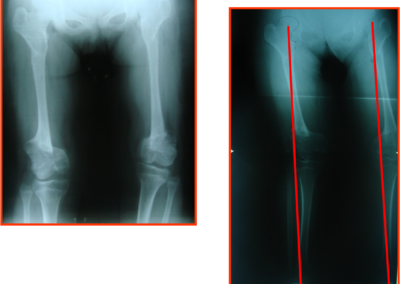

arthritis deformity surgery endoprosthesis hip prosthesis ilizarov ilizarov surgery infected nonunion knee prosthesis lengthening surgery limb lengthening surgery nonunion periprosthetic infection psodoartroz revision surgery total hip prosthesis total knee prosthesis